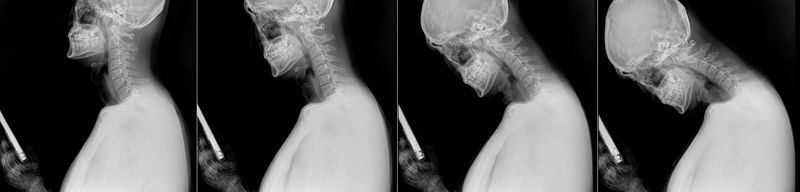

스마트폰 이용 시 목의 변화 X-ray